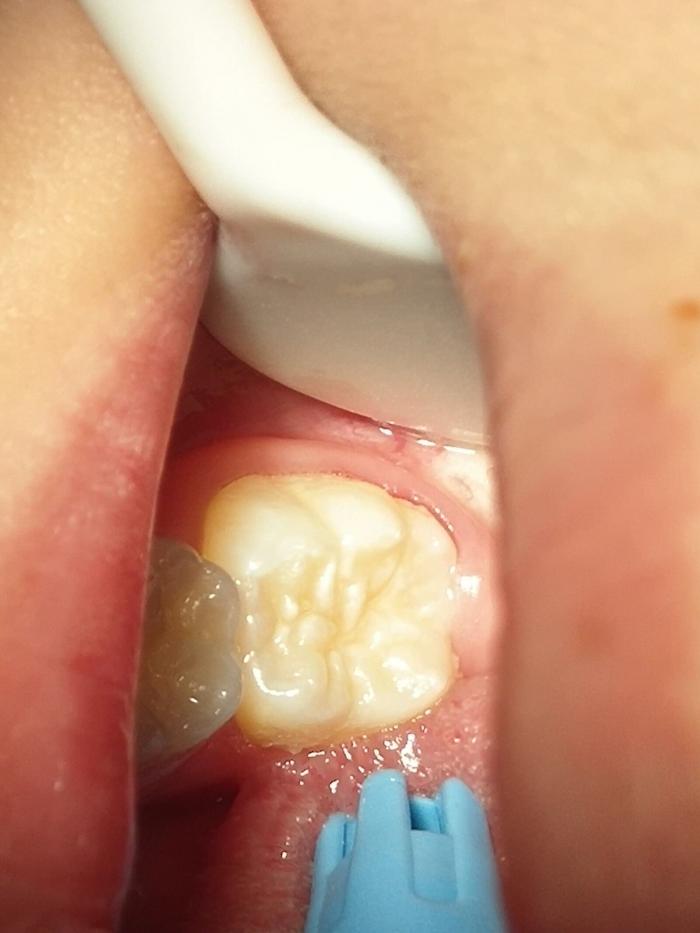

窝沟封闭对于“六龄牙”的保护尤为重要。六龄牙是6岁左右的宝宝在其乳牙的最后方长出的恒牙。这是人生中最为重要的牙齿,由于萌出时间早,使用时间长,再加上其牙齿上面有丰富的窝沟,极易发生龋齿。因此,对其的防护有着极其重要的意义。恒磨牙刚刚萌出1~2年内,是最易发生龋坏的时期,在此期间做窝沟封闭,越早效果越好。

![]()